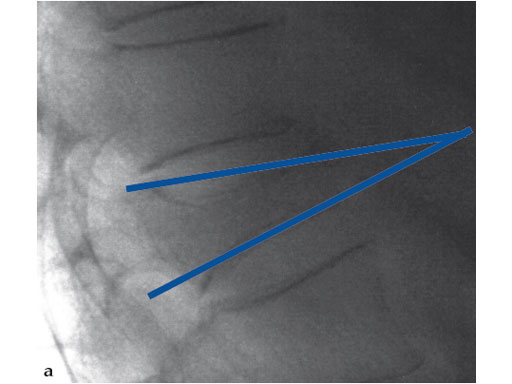

A 78-year-old man with back pain after a simple fall. An MRI showed a subacute fracture with a collapsed vertebral body of L1. A VB S was used for height restoration. The patient was pain-free immediately after the intervention.

Fig 1-4 Intraoperative images.